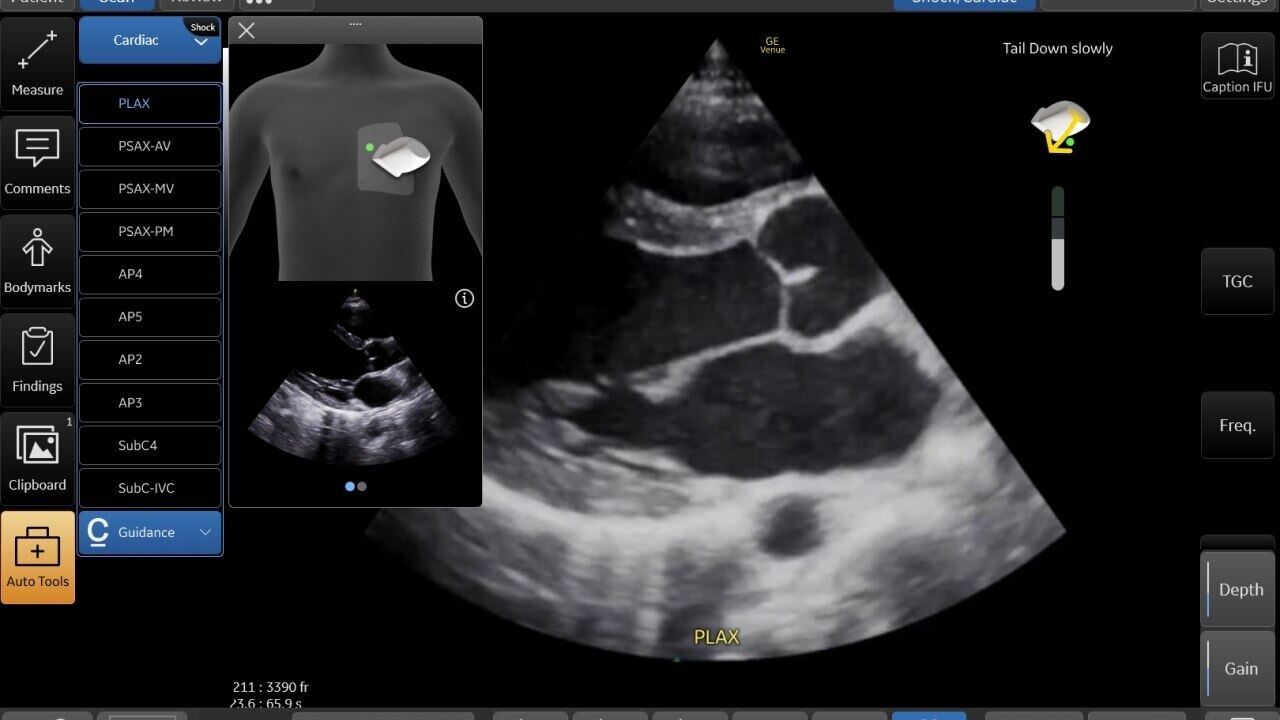

Caption Guidance

Scan with confidence: The right tool in the right hands for cardiac ultrasound in critical moments

Thanks to Caption Guidance™ AI-driven software on the Venue family, even new POCUS users can capture cardiac images successfully. The on-screen, AI-based tool aids with turn-by-turn probe placement to capture the needed views.